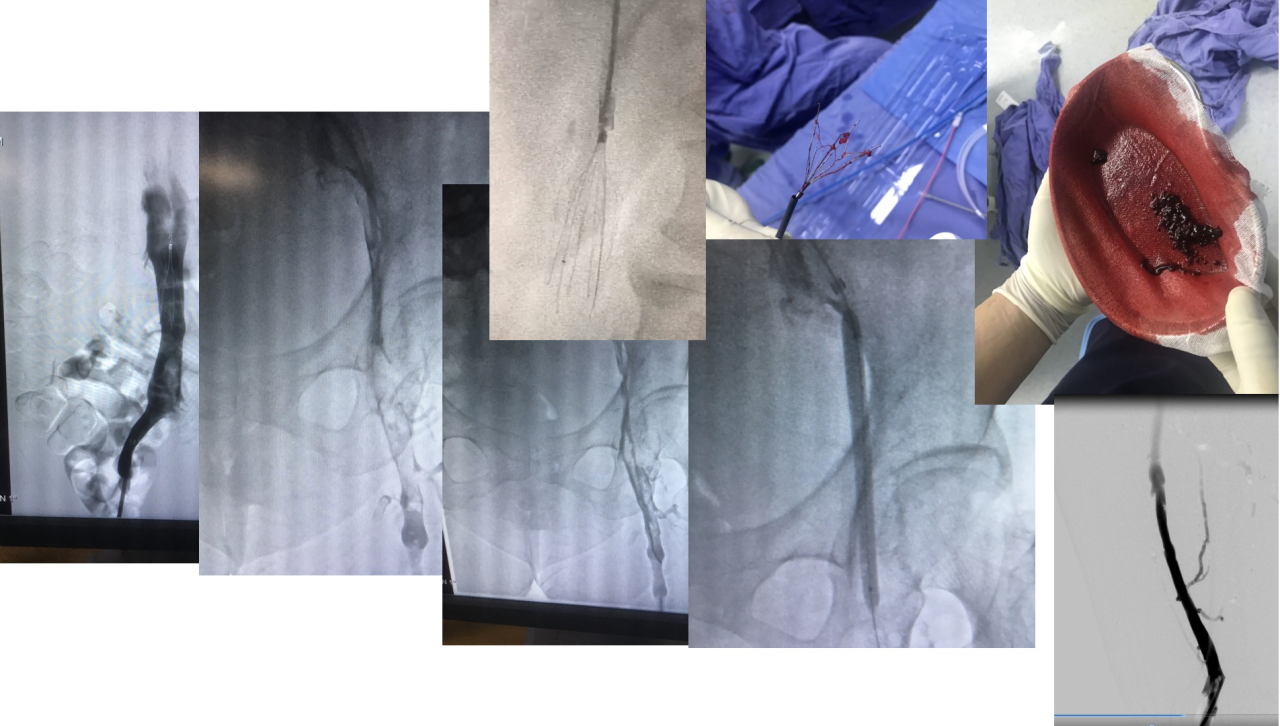

静脉造影:静脉造影是诊断深静脉血栓的“金标准”。但静脉造影是一种有创检查,因此通常在其他检查方法不能明确诊断或治疗时才使用。

导管溶栓术:将溶栓药物通过导管直接注入血栓部位,提高溶栓药物的浓度,增强溶栓效果,减少全身用药的副作用

血栓抽吸术:通过导管将血栓抽出体外,迅速恢复静脉的通畅

下腔静脉滤器置入术:对于存在肺栓塞高风险的患者,医生会建议置入下腔静脉滤器,下腔静脉滤器可以拦截脱落的血栓碎片,防止其进入肺动脉,降低肺栓塞的发生风险。